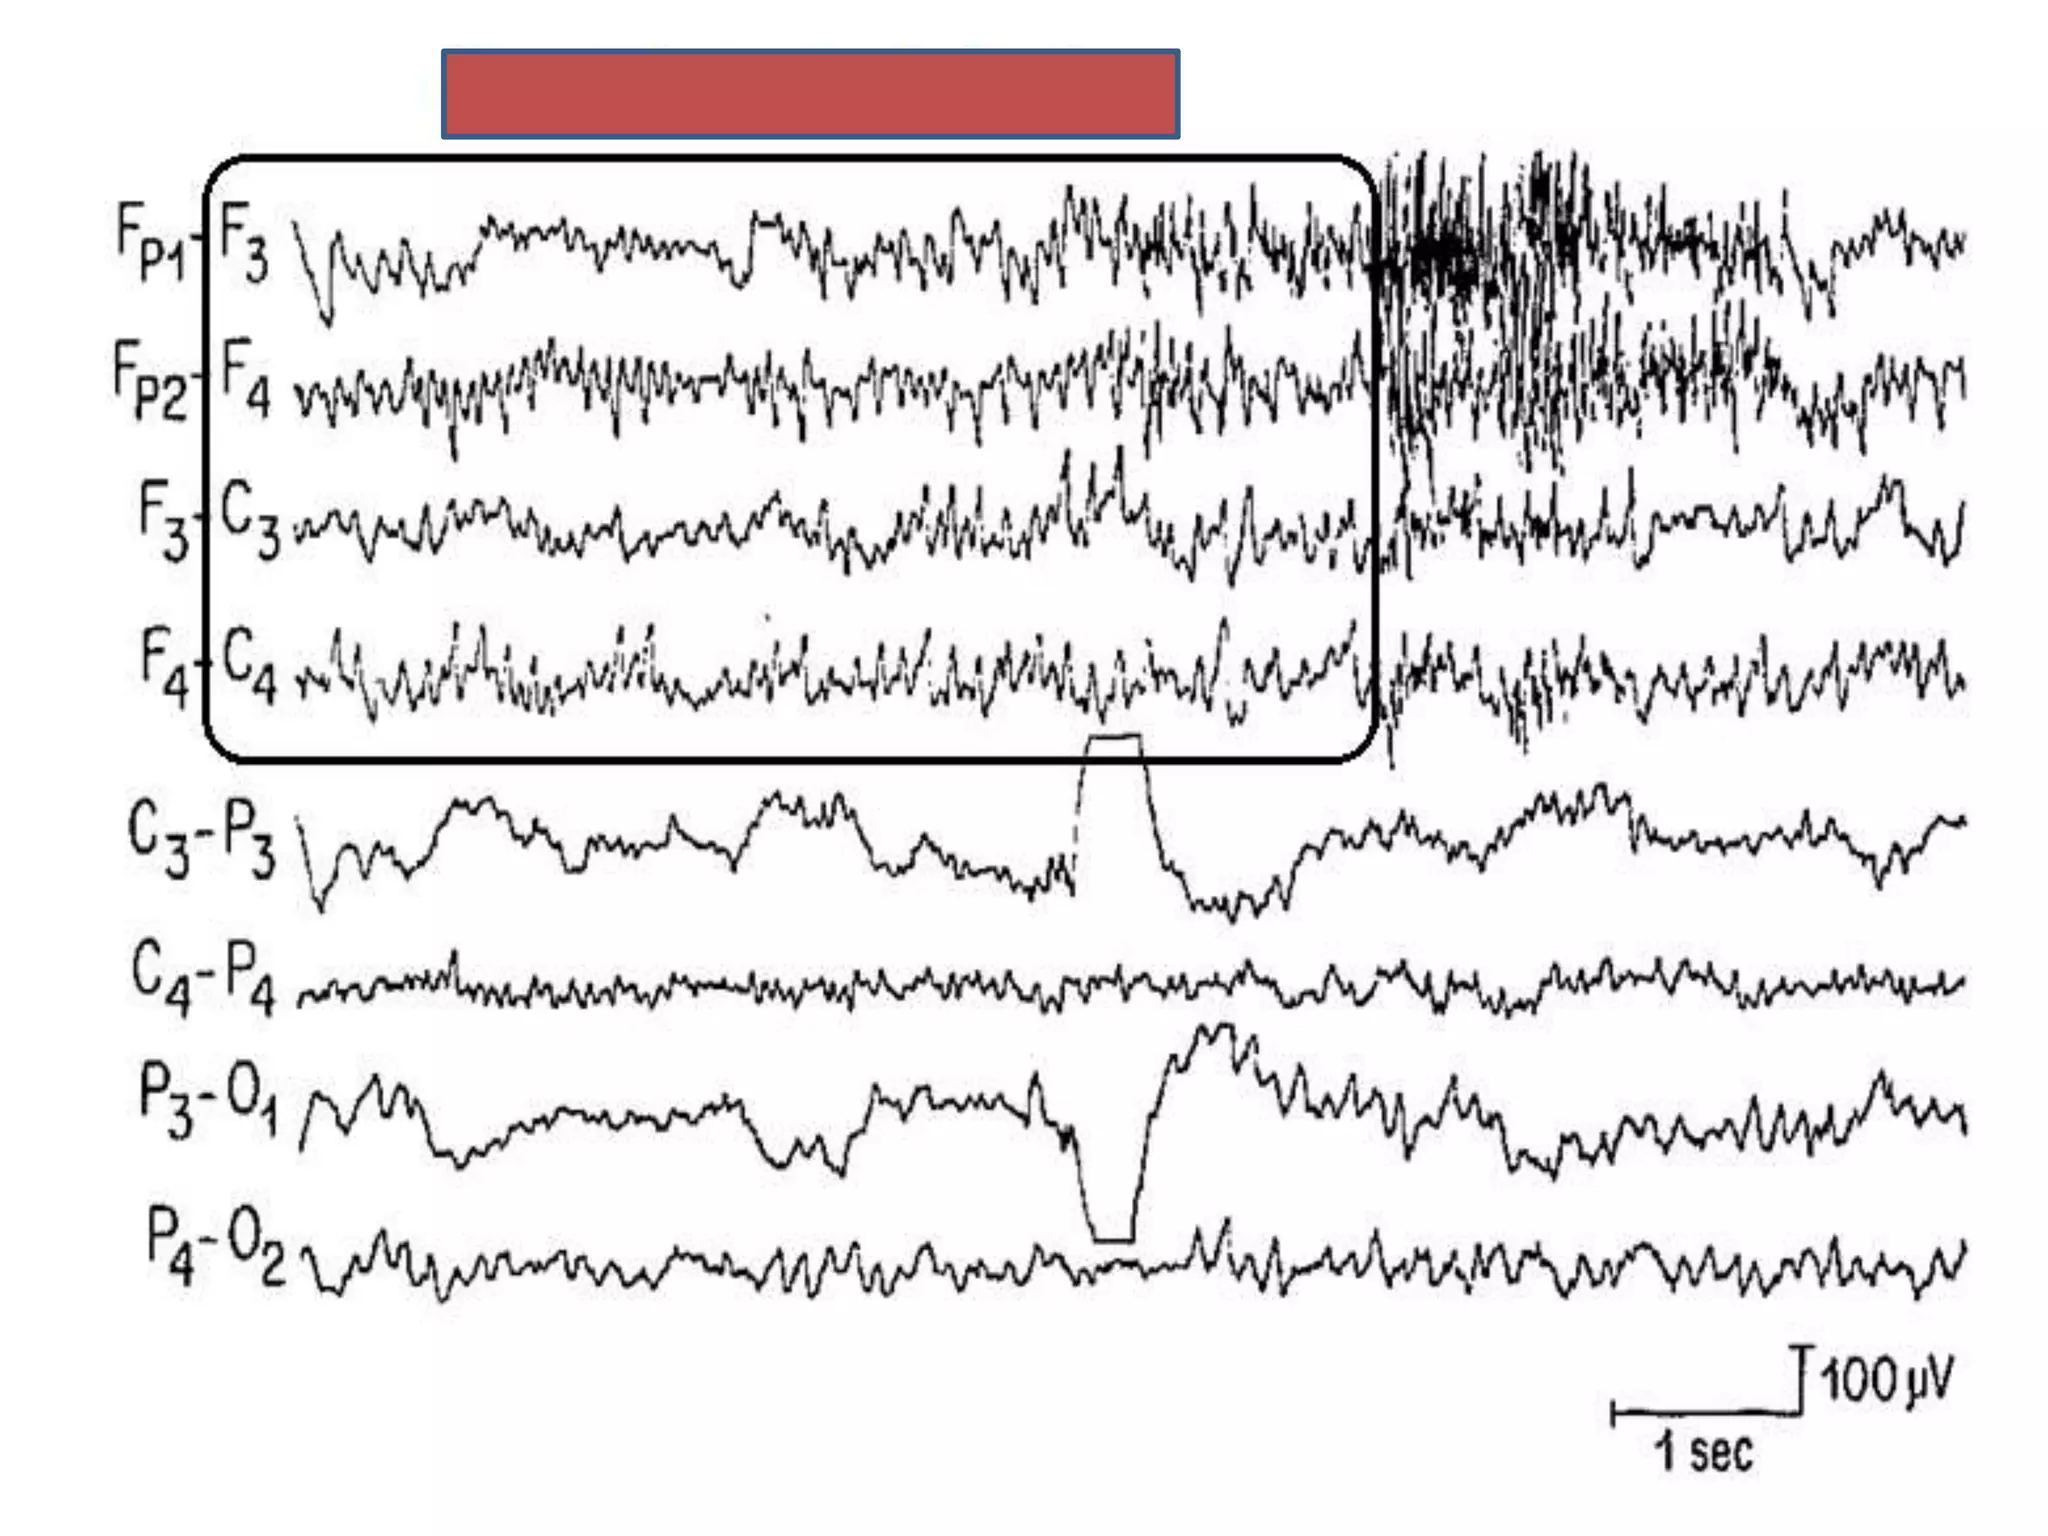

Vertex sharp wave

• Generally diphasic ,sharply contoured.

• Maximum amplitude at C3 & C4 lasting upto 200 ms.

• Initial deflection surface negative f/b slower & lower voltage positive

wave.

• Maximum at the vertex (like K complex)

• Amplitude: 50-150 microV

• Presence in non-REM 1 and to a lesser extent in non-REM 2

• Narrower and more focal than K complex

• Unlike K complex vertex waves are not associated with sleep spindles

.

Vertex sharp wave •Generally diphasic ,sharply contoured. • Maximum amplitude at C3 & C4 lasting upto 200 ms. • Initial deflection surface negative f/b slower & lower voltage positive wave. • Maximum at the vertex (like K complex) • Amplitude: 50-150 microV • Presence in non-REM 1 and to a lesser extent in non-REM 2 • Narrower and more focal than K complex • Unlike K complex vertex waves are not associated with sleep spindles .